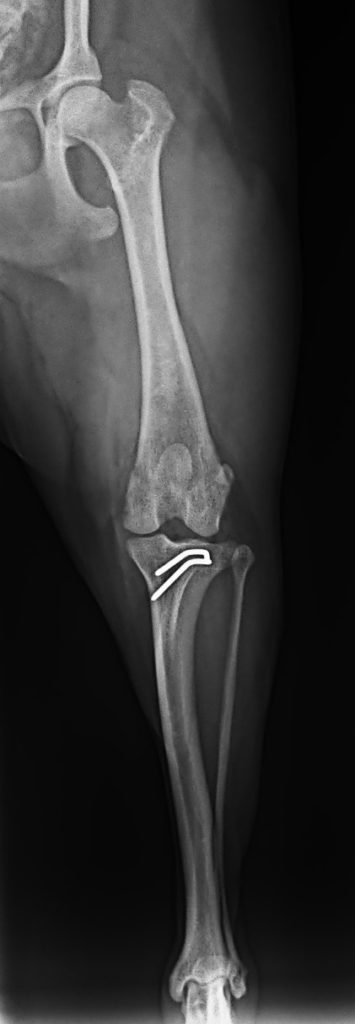

・前十字靱帯断裂の手術(TPLO)

※TPLO=Tibial Plateau Leveling Osteotomy(脛骨高平部骨切り術)

・TPLO(前十字靭帯断裂に対する脛骨水平化骨切り術) 45万円前後